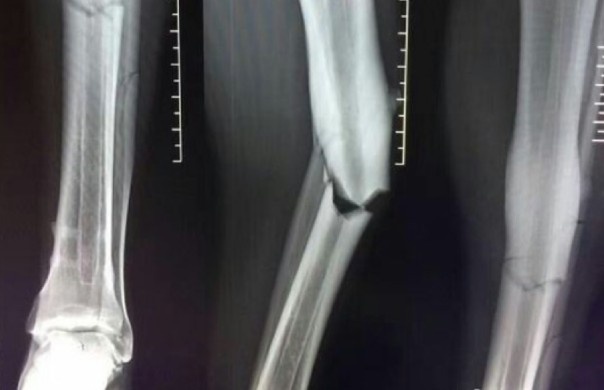

Xương ống đồng chân trái của chân sút 31 tuổi thực sự đã gãy gập sau pha va chạm với cầu thủ đối phương.

Luke Shaw chỉ là một trong số rất nhiều nạn nhân của những pha vào bóng mang tính triệt hạ từ các đồng nghiệp bên phần sân đối diện.

Tiền vệ gốc Indonesia, Radja Nainggolan có pha vào bóng quyết liệt khiến chân phải của tài năng trẻ Federico Mattiello gãy gập ở trận đấu giữa Chievo và AS Roma.

Tiền vệ trẻ Ricardo Centurion của Racing Club lĩnh trọn cú vào bóng các ý từ phía sau của hậu vệ phải Leandro Marin bên phía Boca Juniors trong một trận giao hữu.

Tiền vệ Gilles Yapi-Yapo của FC Zurich có thể chấm dứt sự nghiệp thi đấu sau cú vào bóng kinh hoàng của cầu thủ Sandro Wieser bên phía FC Aarau trong trận đấu thuộc vòng 15 giải VĐQG Thụy Sỹ.

Trong nỗ lực đi bóng xuống biên, Nicusor Bancu (Craiova) bất ngờ bị hậu vệ Alin Seroni (Viitorul) đạp gãy chân.